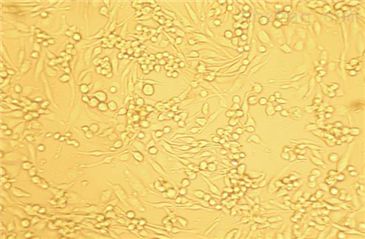

2)形态:上皮细胞样

丁香园网友kj7156084的培养方法: 本室的PC-3来自上海细胞生物所,种是ATCC的。 以10%FBS+1640或F12培养,0.25%胰酶消化。塑料瓶或玻璃瓶都可以,当然,前者效果较好。复苏时最好用塑料瓶。 5-7天传一次(1:2),2-3天换一次液。尽量高密度传,因为PC-3细胞喜欢扎堆长,如果过了两三天细胞长得不均匀,可以消化离心一下。 传代后一到两天不要动它,要有耐心。 人前列腺癌细胞PC-3(高密